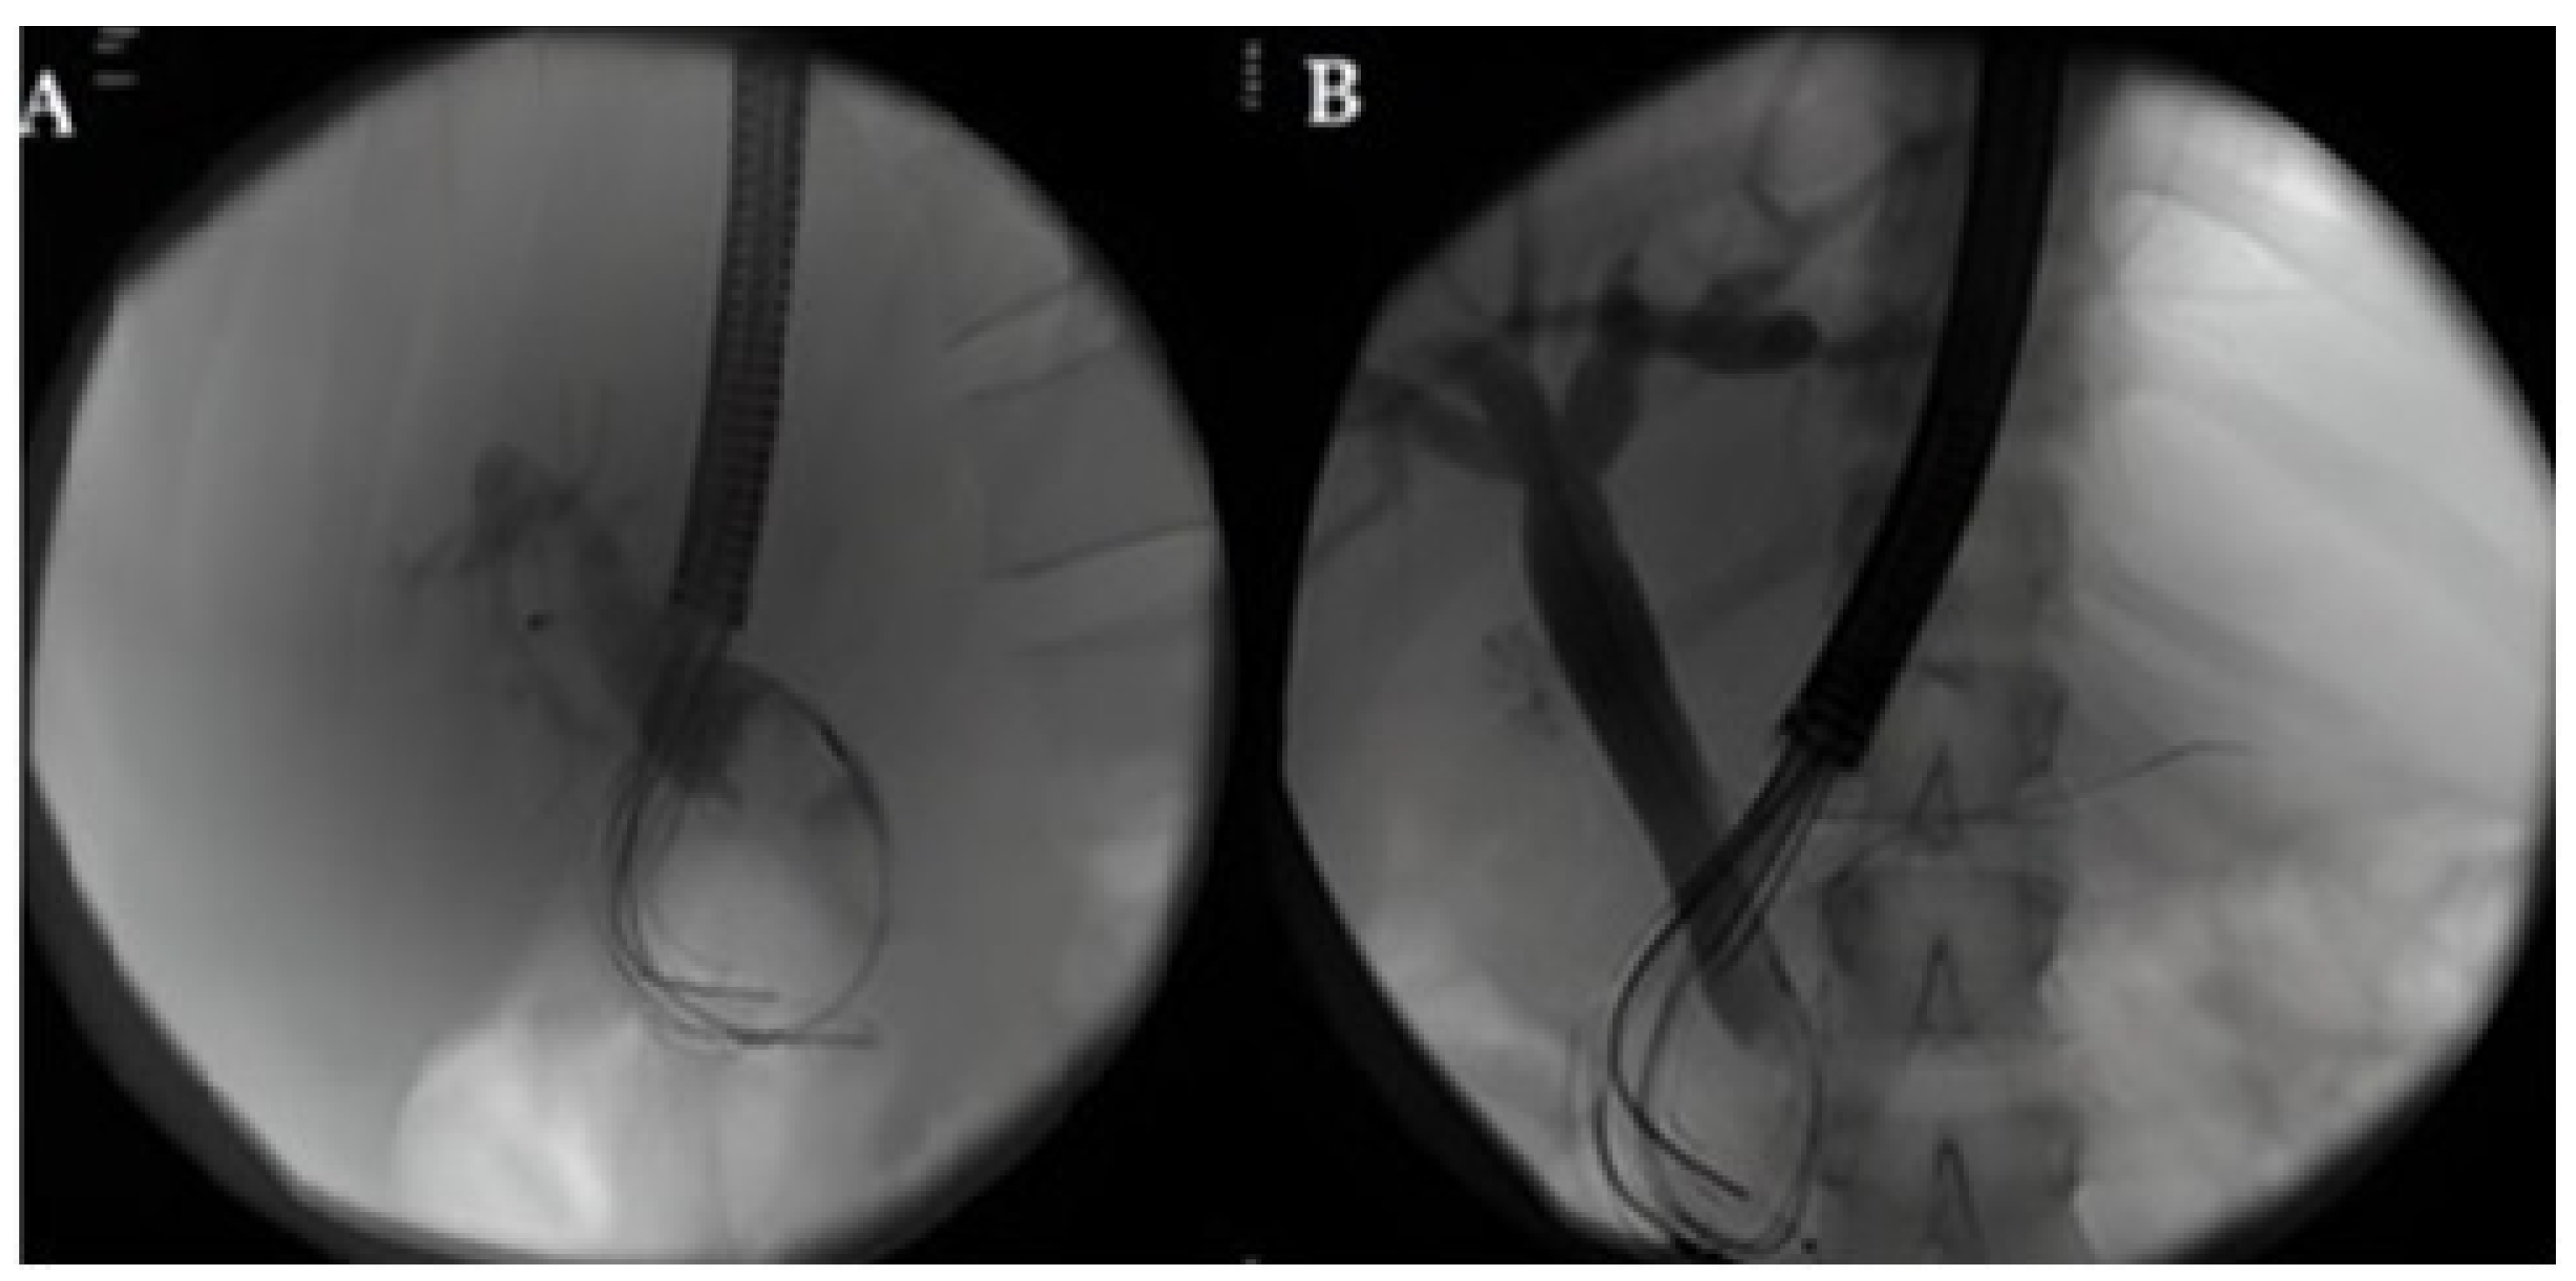

- Rivallin, P.; Lorenzo, D.; Hedjoudje, A.; Prat, F. Single-use duodenoscopes are an efficient tool for emergency ERCP in real life. Endosc. Int. Open 2022, 10, E1497–E1500. [Google Scholar] [CrossRef] [PubMed]